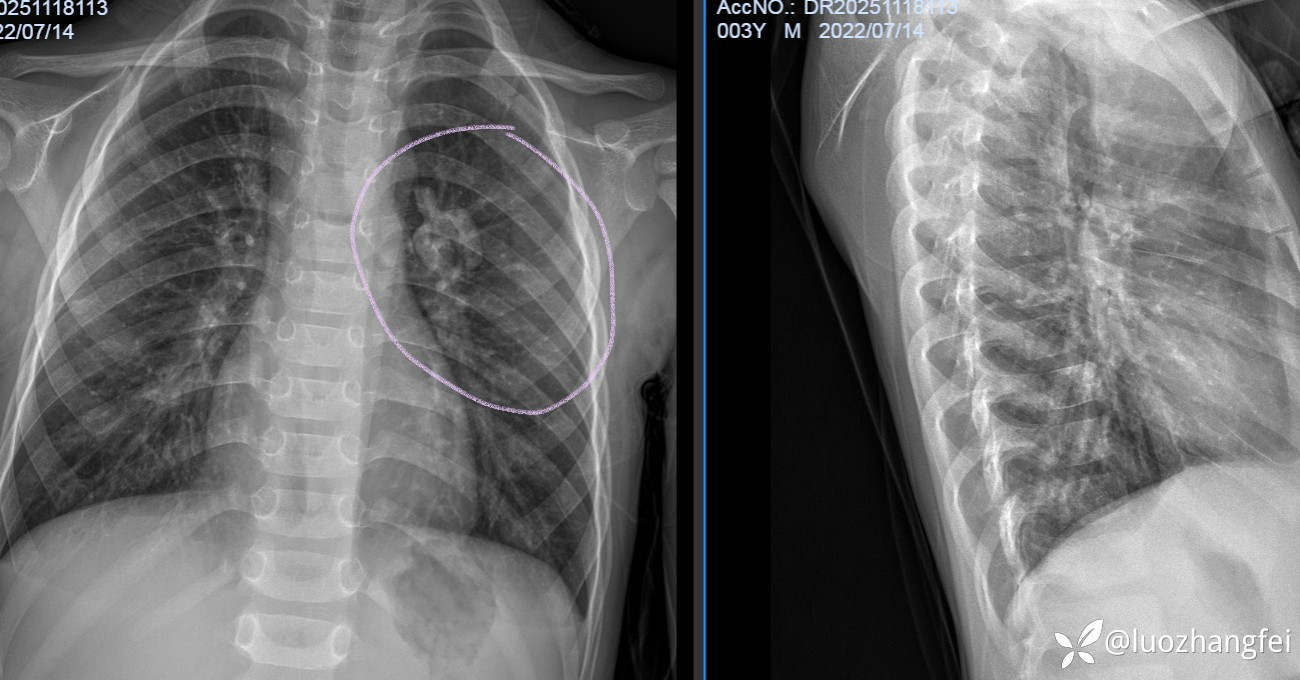

3岁男童胸片惊现“小苹果”显影,会是什么东西呢?

患儿胸片左肺门显影一个“小苹果”,你考虑是什么东西呢?